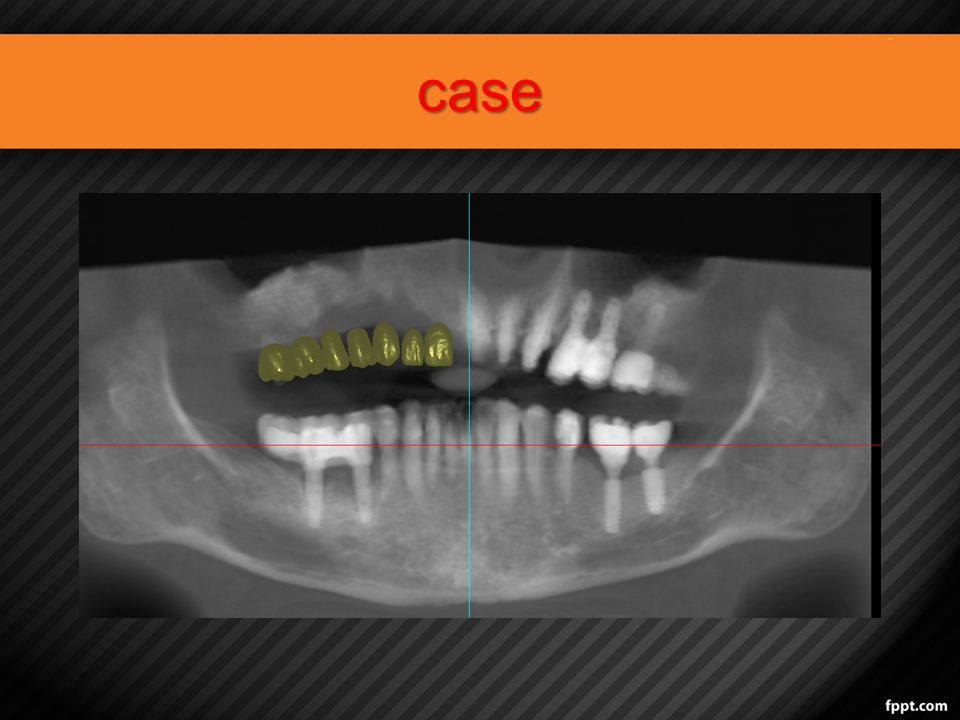

Vertical Alveolar Ridge Augmentation with 3D-Printed Titanium Mesh (30.10.2021)

Case report on vertical bone augmentation using a customized 3D-printed titanium mesh in a complex clinical scenario with prior implant failures. Includes surgical planning, techniques, complications, and an invitation for multicenter research collaboration. Presented by Dr. Levon Galstyan at AAOMFS.